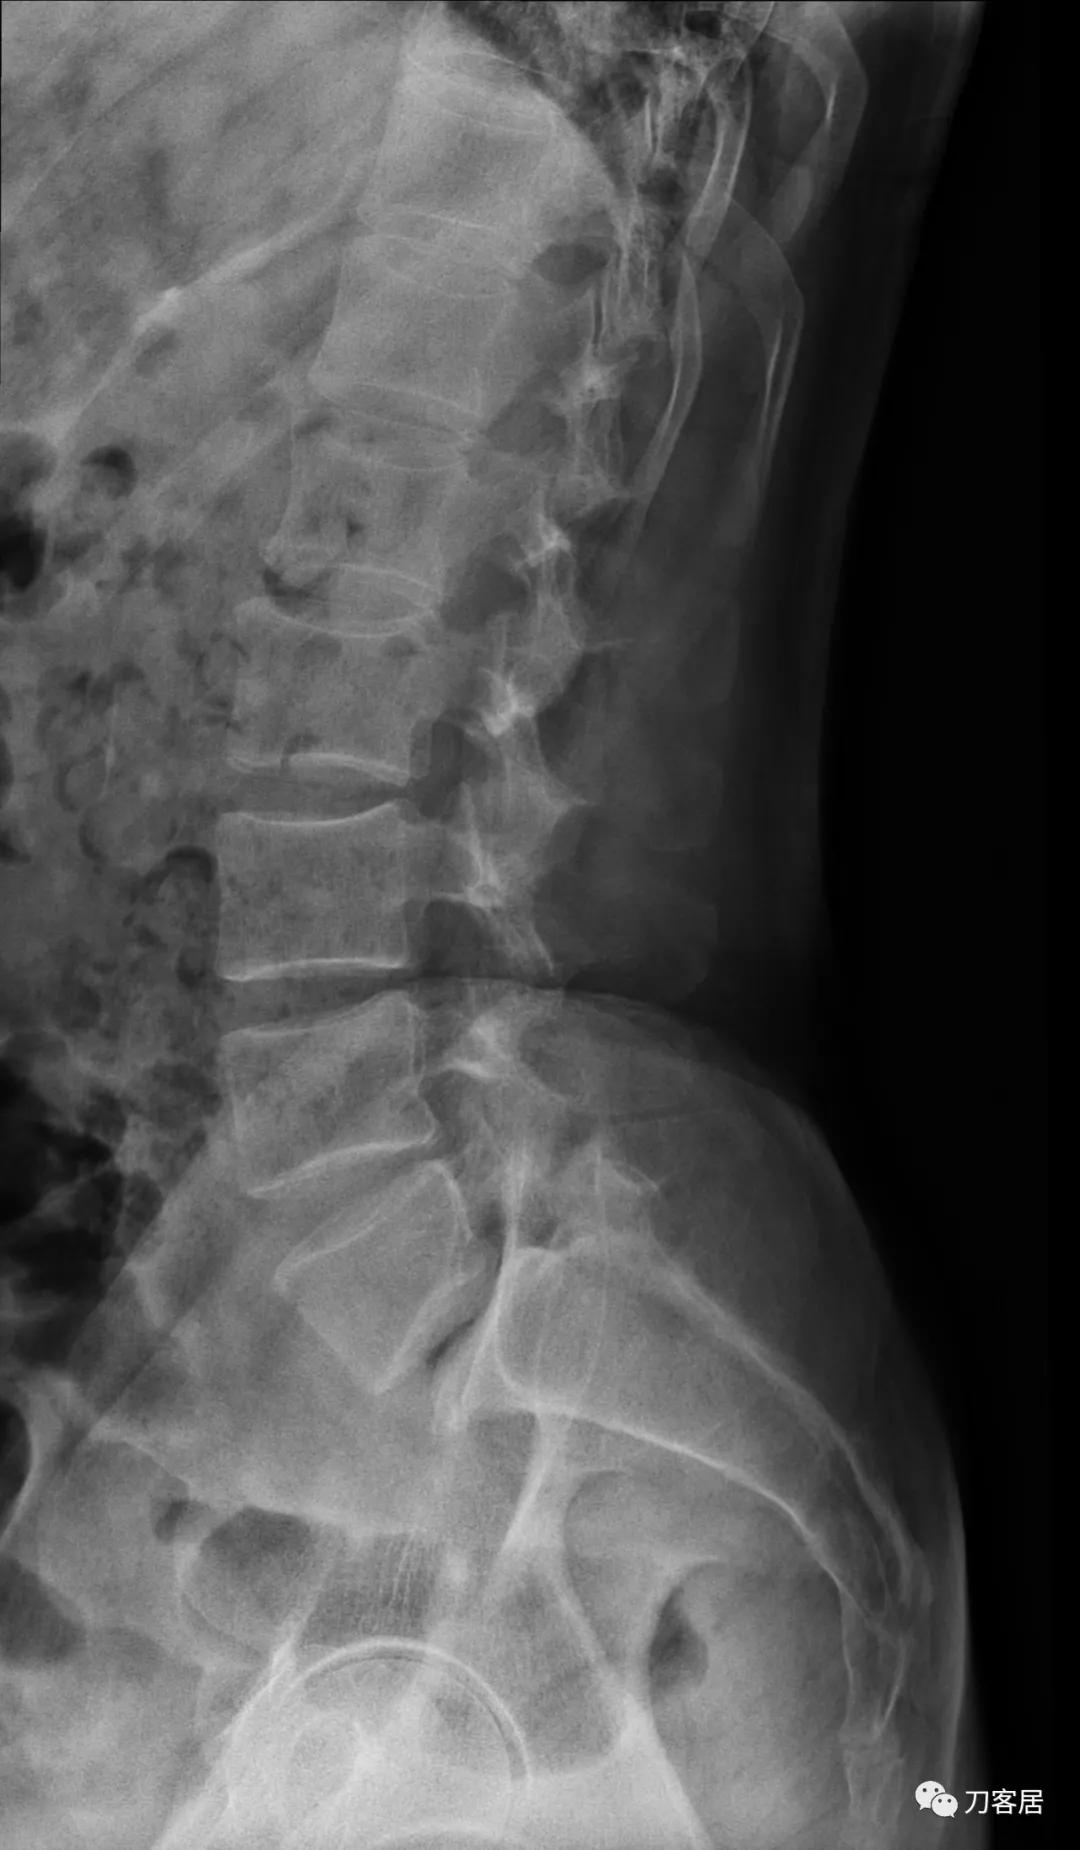

自带影像学检查提示腰5椎体前滑脱,腰5峡部裂,椎管狭窄不严重。

诊断:腰5峡部裂,腰5椎体前滑脱1度,骨质疏松症。

图4. 20210616术前腰椎侧位X线片

图5. 20210616术前腰椎过伸位X线片